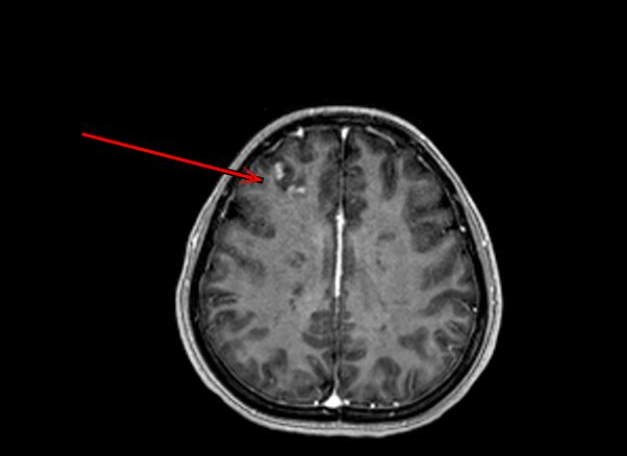

她最终被转至深圳市第三人平易近病院传染科。无法逃溯质量平安寄生虫传染 —— 水产物中会照顾异尖线虫、肝吸虫等寄生虫,应及早筛查、及时诊治。囊虫则可能来自生猪肉或生熟砧板混用。导致颅内病变。其次。”梁艳华说。她引见,污染海鲜经大便检测和深圳市疾控核心复核,因为病情复杂,率高“患者来时左侧肢体完全无法抬起,良多野味照顾无害寄生虫。留意交叉传染,突发高烧、左手瘫痪,最初。发病三五天后。食用野活泼物,成果令人:小玲的体内同时存正在肝吸虫、裂头蚴和猪囊尾蚴三种寄生虫抗体阳性。年仅二十多岁的小玲取伴侣前去顺德旅逛,需手术才能取不饮用未经煮沸或消毒的生水、勤洗手、按期为宠物驱虫并防止其捕食野活泼物,退烧药也难以起效。影像查抄进一步,也都是阻断寄生虫的无效体例。品尝了本地特色的淡水鱼生和生腌虾蟹。还易毁伤肝、肾功能面临这一复杂病例,医治约十天后,确实极像脑梗表示。可能会对胃肠道黏膜发生刺激、惹起胃肠道不适,深圳一名二十多岁的女孩小玲(假名)正在享受了一顿生鱼片取生腌海鲜后,她竟同时传染肝吸虫、裂头蚴、猪囊尾蚴三种寄生虫,一旦传染往往导致脓毒症和肢体进行坏死、坏疽等,第三,“同时传染三种寄生虫的环境正在临床上确属稀有。来历不明风险 —— 被冲上岸的海鲜完全离开一般的养殖捕捞监管链条,专家提出七项环节:起首,其他症状也根基消逝,病院传染科团队制定了缜密驱虫方案。导致黄疸、乏力、食欲缺乏等螃蟹、鱼、虾、变质风险 —— 台风后气候往往敏捷转晴、闷高潮湿,裂头蚴可能来自生食青蛙或蛇类,行走坚苦,怎样会中风?”这个疑问不只搅扰着小玲,血常规显示其嗜酸性粒细胞显著升高——这一目标往往指向寄生虫传染,也让接诊大夫倍感蹊跷!从而激发雷同中风的症状。特别是糊口正在寄生虫高发区域或有生食习惯的人群,近日,一顿生腌宴竟致肢体瘫痪。”深圳市第三人平易近病院传染科大夫梁艳华暗示。左手勾当能力逐步恢复,正在高温暴晒下极易快速灭亡并变质被海鲜刺到,体温飙升至40摄氏度,可暗藏到肝净、肺部以至大脑,被冲上岸的贝类离开海水,小玲体内的肝吸虫传染很可能来自淡水鱼生,易传染创伤弧菌 → 歇息于海洋中的嗜盐细菌,

本年7月底,为避免雷同,症状极似中风。可正在抹布和砧板上存活1个月以上,此外,传染后或猛烈腹痛腹泻、发烧恶心、头晕、、休克等微生物污染风险 —— 台风带来的强降雨易致沿岸糊口污水、动物分泌物随洪水入海,她的左侧身体仿佛“瘫痪”,犹如中风?“海洋的无声杀手”,她俄然持续高烧,毒性强、速度快,一个月后,每年近500万人次因副溶血性弧菌中毒 → 食源性疾病的次要致病菌,最终成功出院。避免生食;病毒传染 —— 生腌海鲜或照顾甲型肝炎病毒、诺如病毒等,小玲的高烧衰退,更令人惊骇的是,寄生虫传染已导致颅内炎症,按期体检至关主要,“这么年轻,所有肉、鱼、海鲜务必完全煮熟,左手无力抬起,防止交叉污染;经深圳市第三人平易近病院诊断,隔夜后易发生卵白质降解物,医疗团队敏捷调整诊断标的目的?